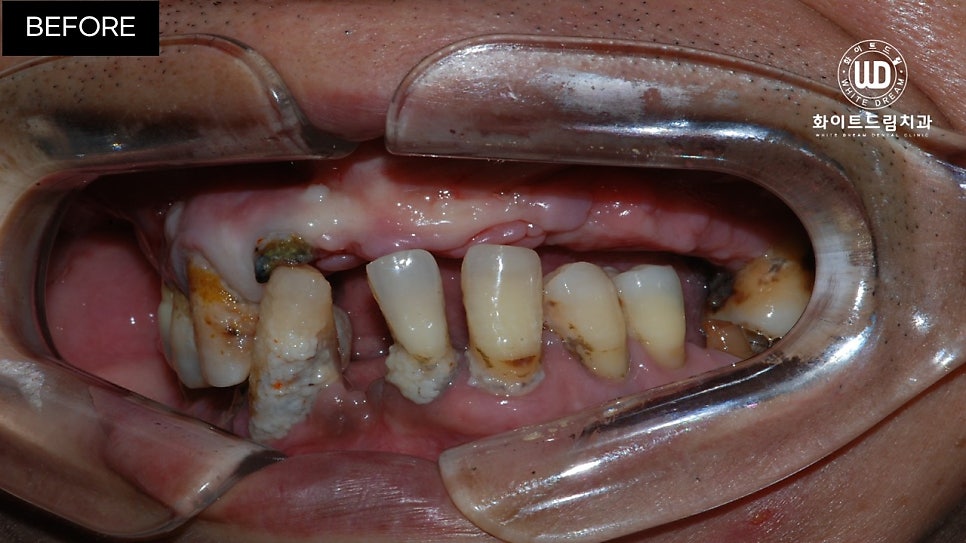

오늘 말씀드릴 환자분은 이전 케이스들과는 달리 보존된 치아는 많지만 전체적으로 흔들리는 등 상태가 좋지 않아 내원하셨다고 합니다.

해당 환자분은 전체발치 / 40대임플란트 / 전체임플란트식립 환자분이었습니다.

임플란트 식립 전 상, 하악 모습입니다.

육안으로 보이실지 모르겠으나 잔존한 치아 주위염이 심한 상태셨는데요. 뿐만 아니라 치아 파절과 함께 영구치의 뿌리 대부분이 손상되어 있는 상태였습니다.

이미 발치되어 있는 쪽은 치아가 소실된지 오랜 시간이 지나 잇몸뼈가 부족한 상태였고, 현 상태로는 픽스쳐를 식립할 수 없어 전체 발치 후 상악 양측 구치부 상악동 거상술 및 전체 치조골 이식을 동반한 전체 임플란트 식립을 진행하기로 했습니다.